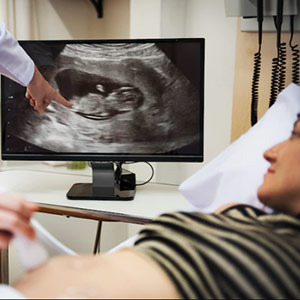

Sonomammo

The best gynaecologist might often ask you to get a sono mammography done. Itrefers to the ultrasound of your breast, and it is a non-invasive procedure that checks the health of your breasts and the flow of blood to the areas inside them. It is an imaging technique that screens and examines for cancer and other abnormalities of the breast. This test allows the quick visualization of your breast tissue. The examination is done with mammography or the X-ray of your breast tissue to study a lump or mass.